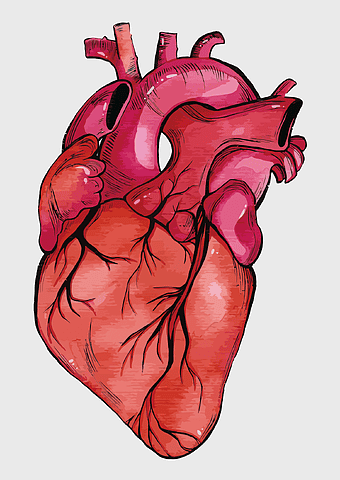

Heart Anatomy Diagram, human heart drawing, realistic heart illustration, cardiovascular system, medical illustration, organ structure, human anatomy study -

human heart anatomy, cardiovascular system illustration, medical heart diagram, heart organ structure, human body organ visuals, anatomical heart drawing, heart health -

human heart anatomy, red heart illustration, heart organ diagram, heart muscles and valves, cardiovascular system diagram, human body organ chart, anatomical heart structure -

human heart illustration, cardiac anatomy diagram, heart blood vessels, medical organ visuals, cardiovascular system chart, human anatomy study, circulatory system illustration -

human heart anatomy illustration, watercolor heart painting, heart shape medical care, red heart organ, cardiovascular system diagram, anatomical heart drawing, heart structure analysis -